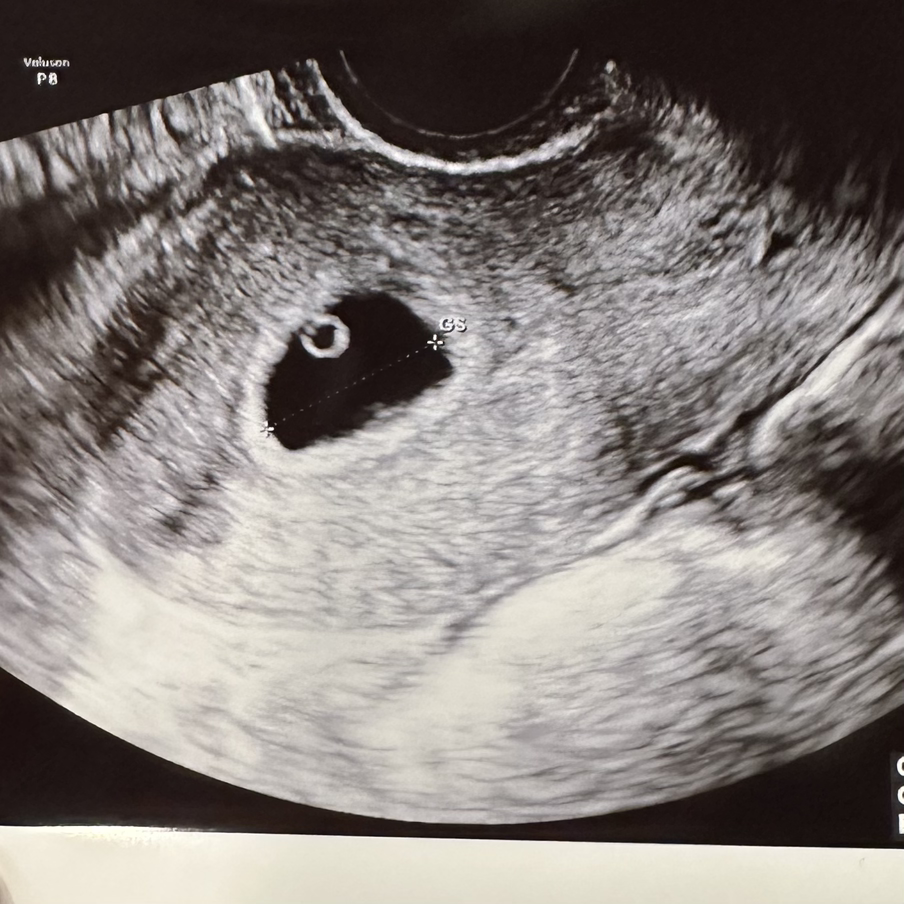

토요일 아침 일찍 눈뜨자마자 산부인과로 향했다. 첫 초음파를 하는 날이었다. 검사를 시작하자마자 모니터에 땡그란 동그라미가 보였다. 이리저리 초음파 기계를 돌려봐도 저 땡그라미가 사라지지 않았다. 내 첫 소감은 ‘땡그랗네요’였고, 의사 선생님 첫마디도 ‘땡그랗죠’였다. 의사 선생님께서 설명하시기를, 난황이라고 하셨고 위치와 모든 것이 좋다고 하셨다. 친구와 가족들에게 초음파사진을 보냈고, 사촌 언니는 땡그란 사진을 보며 ‘벌써부터 귀엽네’라고 해줬다. 땡글~